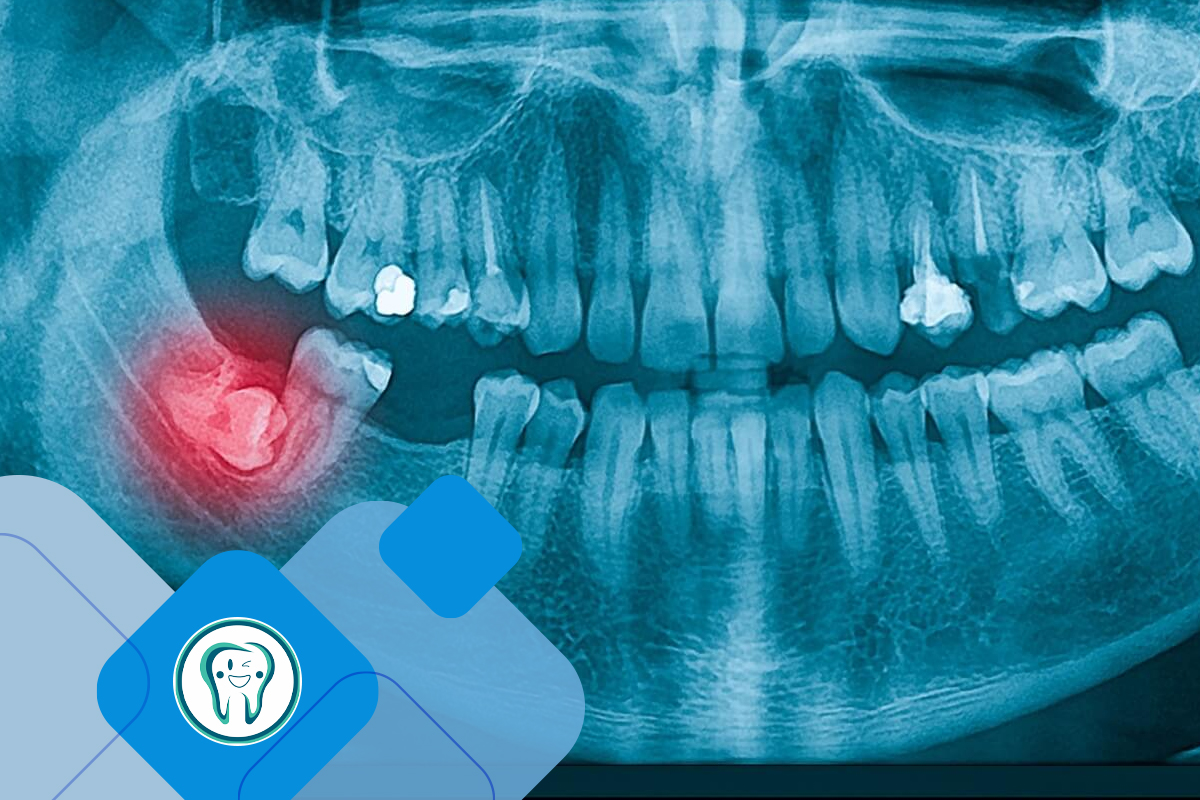

دندانپزشکان از ترکیبی از معاینه بالینی و تصویربرداری رادیوگرافیک برای تشخیص دقیق دندان عقل تحت فشار استفاده میکنند. اولین گام، معاینه کامل دهان است تا علائمی مانند قرمزی، تورم، محدودیت حرکت فک، یا مولرهای نیمهرشد کرده در انتهای دهان شناسایی شوند. اگر علائمی مانند درد، نامنظمی ، یا عفونتهای مکرر وجود داشته باشد، دندانپزشک به احتمال وجود دندان عقل تحت فشار مشکوک میشود.

تشخیص قطعی با استفاده از رادیوگرافیهای دندانی، بهویژه تصاویر پانورامیک یا توموگرافی کامپیوتری (CBCT)، تأیید میشود. این تصاویر موقعیت، عمق، زاویه دندان (عقل) تحت فشار و نزدیکی آن به ریشههای مجاور، اعصاب، و سینوسها را نشان میدهند. این فرآیند به دندانپزشک کمک میکند تا نوع تحت فشار بودن (تحت فشار نرم، نیمهاستخوانی، یا کاملاً استخوانی) را تعیین کرده و روش درمانی مناسب را انتخاب کند. تشخیص زودهنگام با این ابزارها نتایج بهتری برای بیمار به همراه داشته و از عوارض جلوگیری میکند.